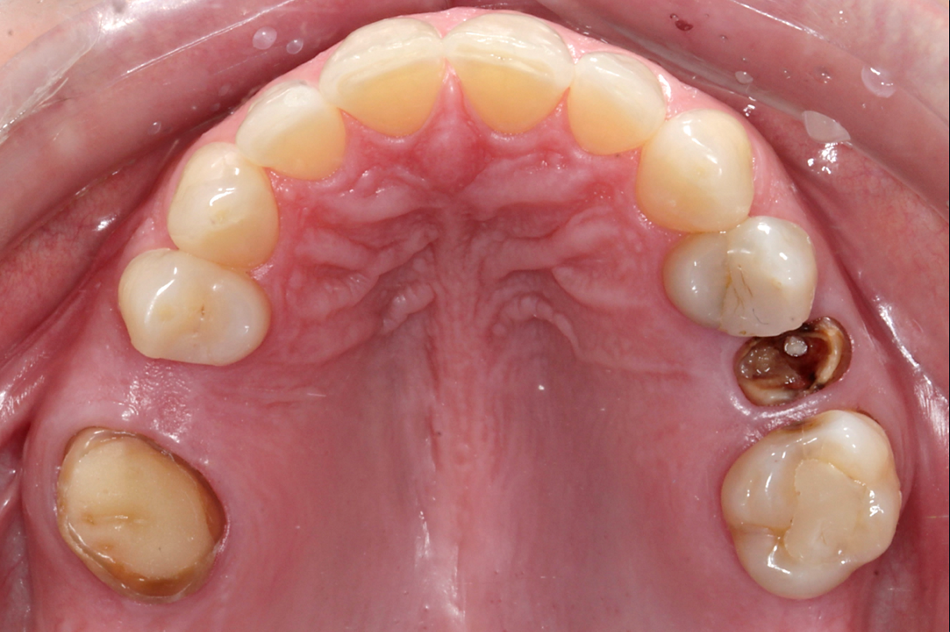

Initial situation

A 38-year-old female patient presented to the dental office reporting discomfort when smiling, due to the absence of both upper second premolars (Figs. 1-3).

Clinical examination revealed tooth #16 with an intraradicular post and preparation for a crown, which was missing. In the adjacent quadrant, a cavity was noted on the distal surface of tooth #14. Overall, the patient exhibited healthy periodontal conditions. She is a non-smoker and does not present with any comorbidities or systemic health issues. CBCT imaging showed no signs of acute infection, and adequate bone quality and quantity at both sites. Additionally, a residual root was identified at site #15 beneath the already healed gingiva.